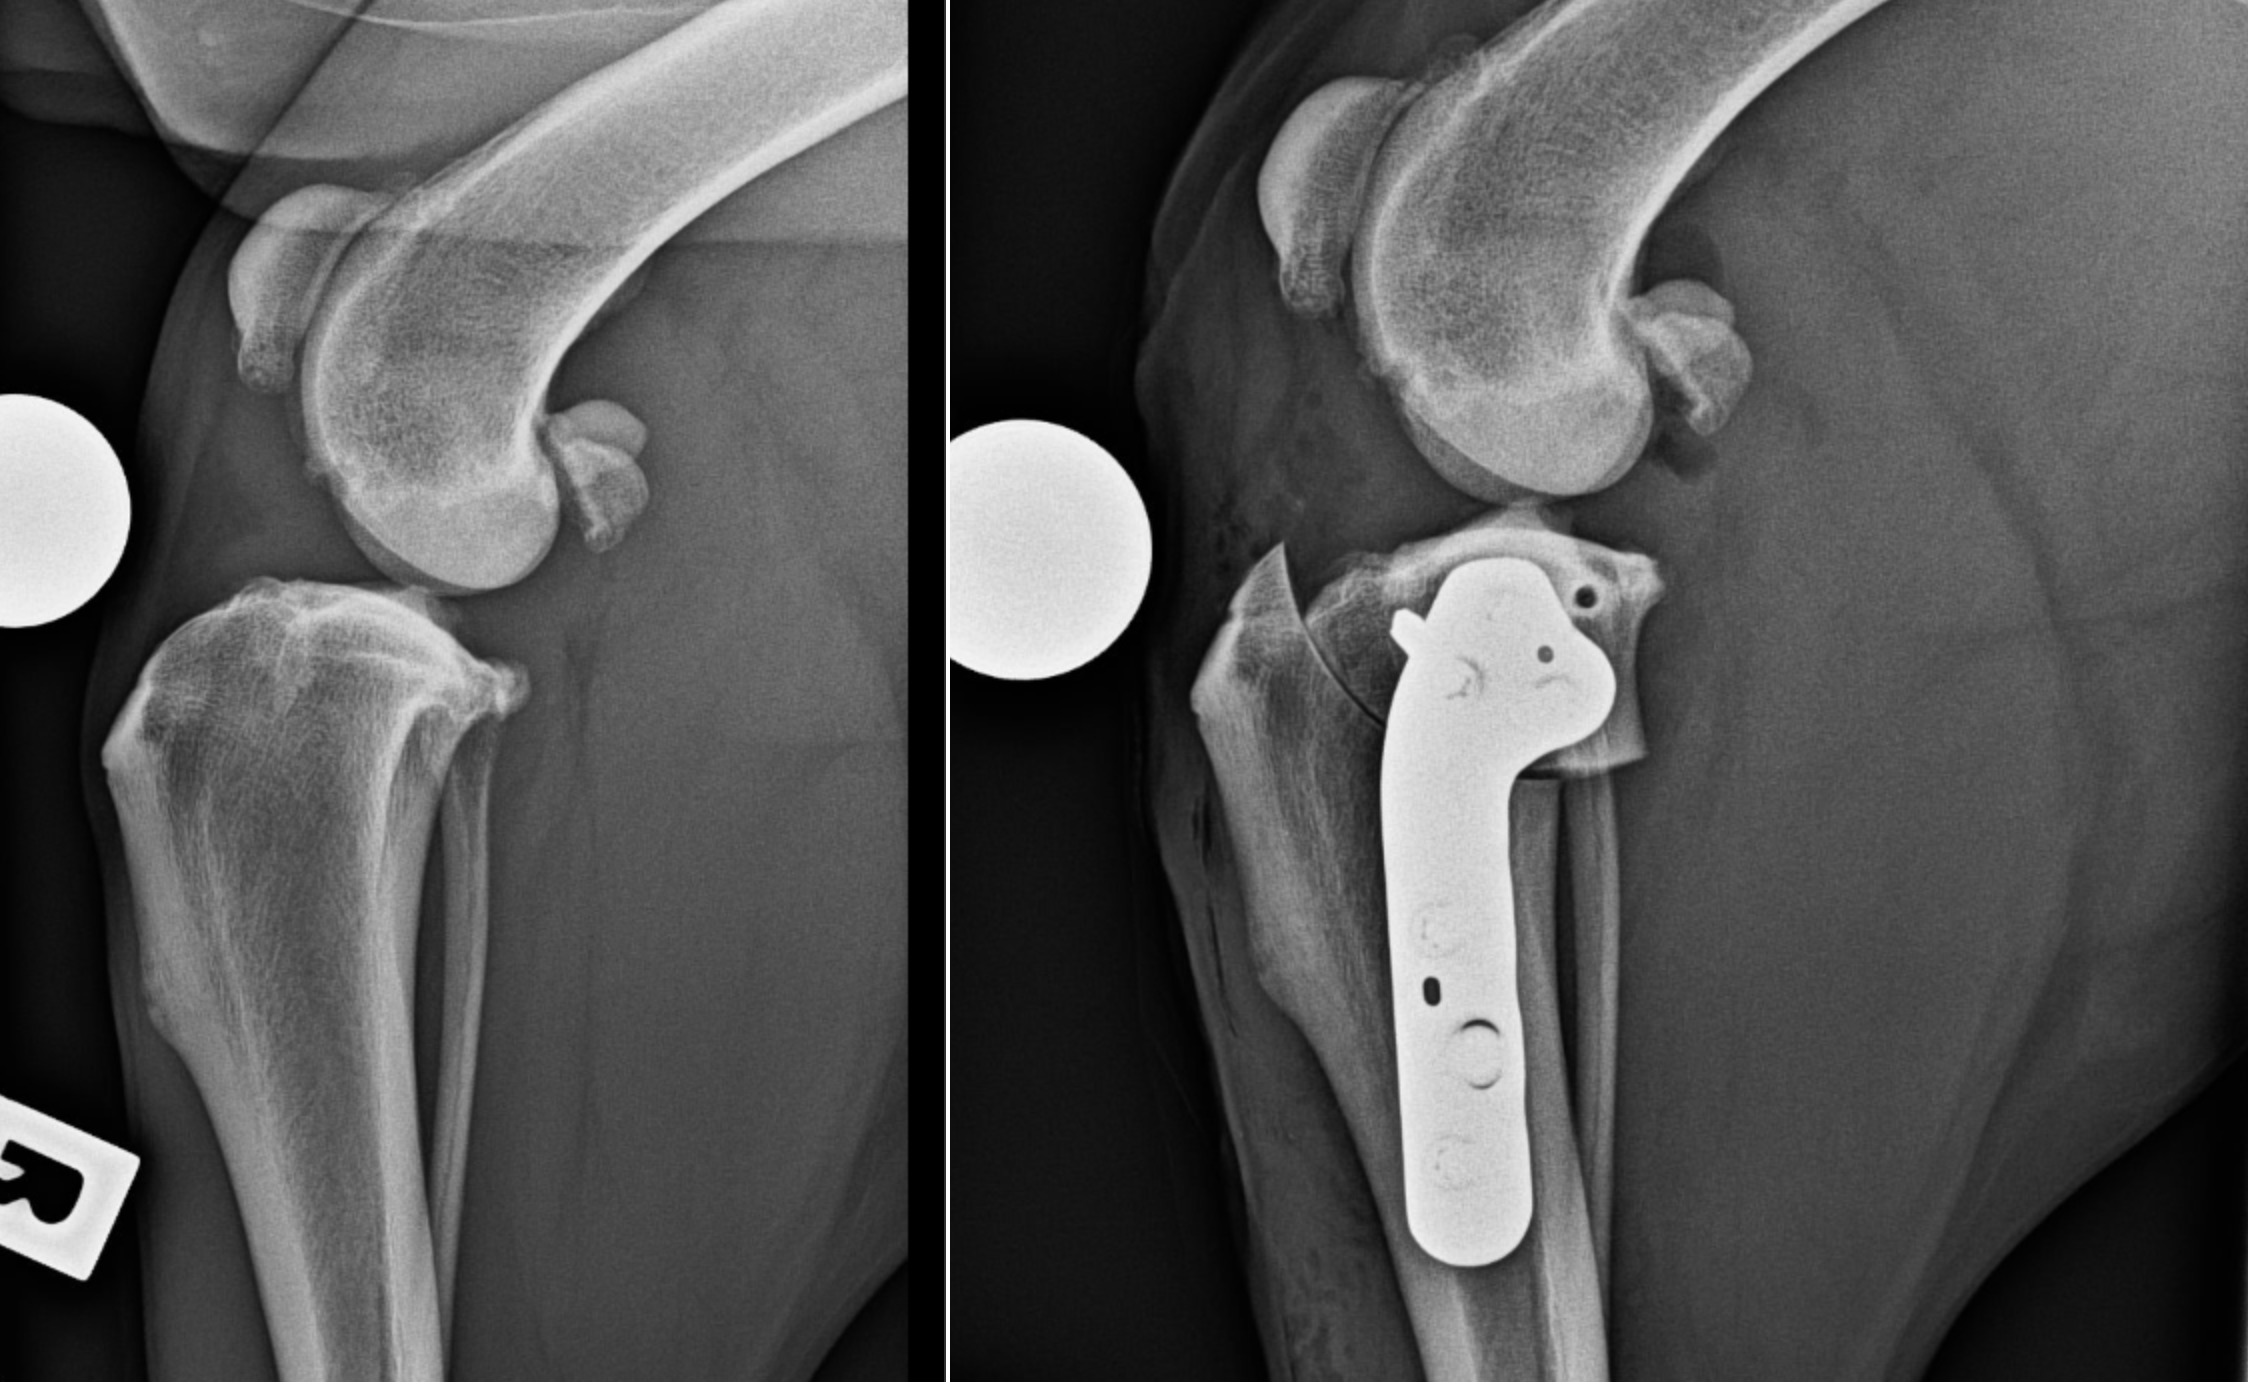

TPLO stands for Tibial Plateau Levelling Osteotomy. It is a surgical technique to restore stability in a knee affected by a cruciate ligament rupture. Rather than repairing or replacing the ligament, TPLO works by changing the slope of the tibial plateau so that it no longer pushes forward when your dog bears weight. That shift removes the need for the ligament to resist forward motion, allowing comfort and normal function to return without an ACL in place.

Compared with other procedures such as Tibial Tuberosity Advancement (TTA), TPLO is well suited to active, large and athletic dogs. The stabilisation comes from a carefully cut and rotated segment of the shin bone, secured with a strong plate and screws. This corrects the biomechanics of the knee and offers long-term relief.

During surgery, under general anaesthesia, the veterinary surgeon makes an incision through the joint capsule. A saw is used to cut the tibia just below the knee. The plateau is then rotated to a more level angle. This realignment reduces mechanical stress and prevents the unwanted forward motion of the shin bone. A custom-fitted bone plate and screws are used to hold the segment firmly in place.